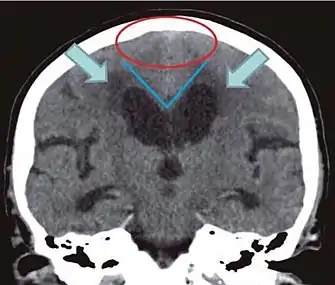

- Imaging from magnetic resonance imaging (MRI) or computed tomography (CT) is needed to demonstrate enlarged ventricles and no macroscopic obstruction to cerebrospinal fluid flow. Imaging should show an enlargement to at least one of the temporal horns of lateral ventricles, and impingement against the falx cerebri resulting in a callosal angle ≤ 90° on the coronal view, showing evidence of altered brain water content, or normal active flow (which is referred to as "flow void") at the cerebral aqueduct and fourth ventricle.

| Normal pressure hydrocephalus | Brain atrophy | |

| Preferable projection | Coronal plane at the level of the posterior commissure of the brain. | |

| Modality in this example | CT | MRI |

| CSF spaces over the convexity near the vertex (red ellipse | Narrowed convexity ("tight convexity") as well as medial cisterns | Widened vertex (red arrow) and medial cisterns (green arrow) |

| Callosal angle (blue V) | Acute angle | Obtuse angle |

| Most likely cause of leucoaraiosis (periventricular signal alterations, blue arrows |

Transependymal cerebrospinal fluid diapedesis | Vascular encephalopathy, in this case suggested by unilateral occurrence |

MRI scans are the preferred imaging. The distinction between normal and enlarged ventricular size by cerebral atrophy is difficult to ascertain. Up to 80% of cases are unrecognized and untreated due to difficulty of diagnosis.[10] Imaging should also reveal the absence of any cerebral mass lesions or any signs of obstructions. Although all patients with NPH have enlarged ventricles, not all elderly patients with enlarged ventricles have primary NPH. Cerebral atrophy can cause enlarged ventricles, as well, and is referred to as hydrocephalus ex vacuo.